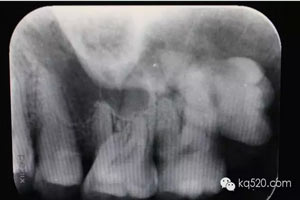

圖2.根尖片檢查:28遠中水平阻生,看不清28牙根與上頜竇的關系,建議拍全景片。